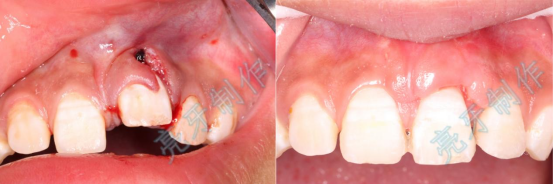

病例一:上门牙外伤,牙齿脱落;再植治疗3个月后,恢复良好。